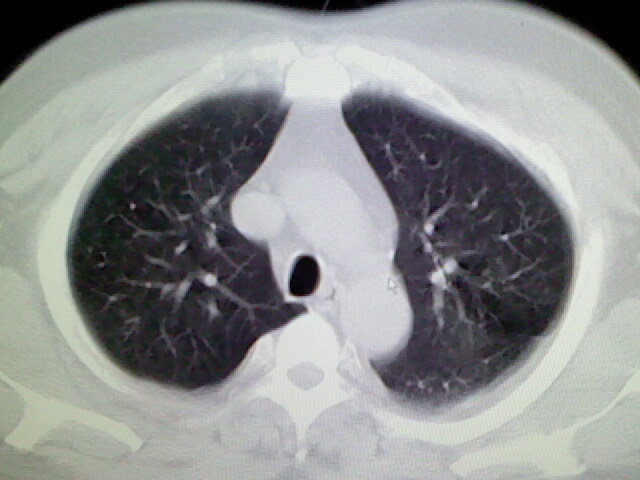

标题: CT17932:临床怀疑肺栓塞 [打印本页]

标题: CT17932:临床怀疑肺栓塞

男,34岁,自觉右侧胸痹,胸闷3天余

两肺纹理增多,余未见明确异常。

右侧肺动脉似见密度稍低影,请在机器的薄层上再看看有没有充盈缺损。